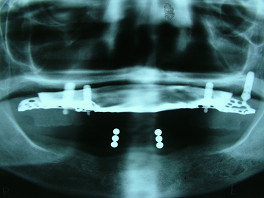

次の方は、歯を全く削らずにきれいにしてほしいということで、大阪から来られた患者さんの左上の前の歯4本を、グラディアで白くしてみました。

歯を全く削らず、表面をナノシールで処理して、グラディアで30分くらいの施術でした。

術前 ↓

術後

右側のすでに被せてある茶色く変色している歯は、大阪の家の近くの歯医者さんで、今回白くなった色に合わせて、被せなおしてもらうとのことです。